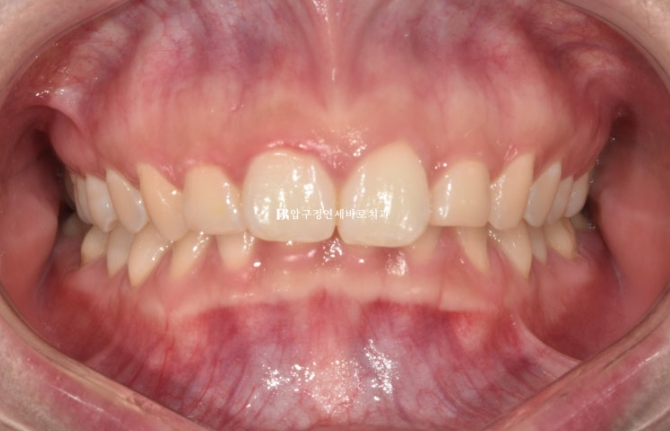

환자분이 고치고 싶은 것은 두가지가 있었습니다.

돌출입과 웃을 때 잇몸이 많이 보이는 거미스마일 이었습니다.

과개교합이 심해서 윗니에 덮여 아래 앞니가 보이지 않습니다.

22.08

돌출입도 종류가 다양한데, 이렇게 앞니가 뻗쳐 있지 않으면서 잇몸쪽이 돌출이 되어 보이는 것을 잇몸돌출이라고 표현합니다.